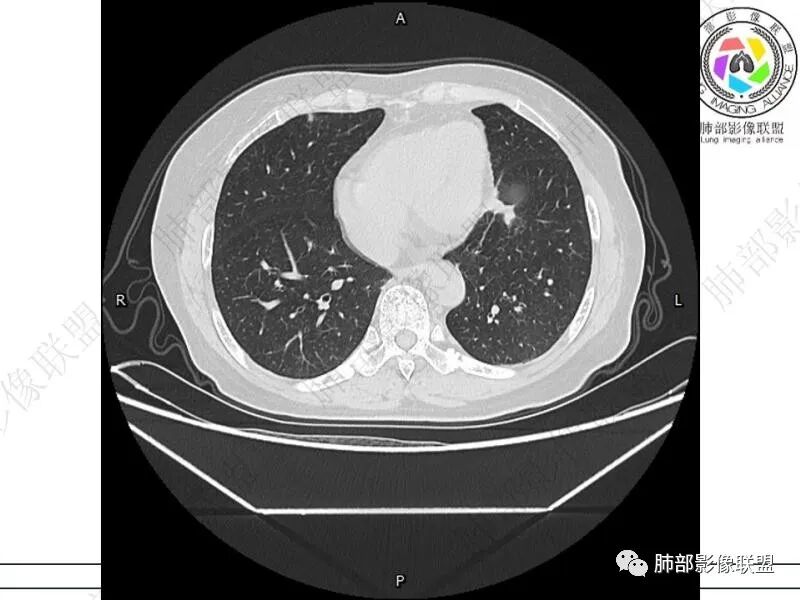

谢加平:结肠癌术后史,两肺胸膜下多发结节及斑块实变病灶,实边边界平直征(亚急性和慢性病变过程),双肺下叶后基底段胸膜下为甚,与胸膜平行特点,见支气管充气征,边缘模糊的GG0,首诊2022年11月18日肺部CT,与治疗11月28日对比,病灶未吸收,双肺下叶胸膜下病灶有侧向融合特点,综合分析符合炎性肉芽肿,隐球菌感染。

老年女性,结肠癌术后。两下肺胸膜下为主片状实变,右下肺短期复查融合且病灶长轴平行于胸膜,实变内可见支气管充气征,边缘磨玻璃晕,另两肺内胸膜下散在数枚小结节状、楔形实性灶。考虑感染性病变,隐球菌可能,鉴别肺转移。

THINKER:胸膜下实变,常见OP丶PC丶PE丶腺癌丶腺病毒丶非典型病原体。1.此例肠癌,免疫妥协人群,PC要考虑,但荚膜抗原阴性,阴性预测值很高。2.肿瘤史,本身易高凝状态,肺栓塞要考虑。3.OP  胸膜下实变,经典型OP影像。故:PE>OP>PC

2.影像特征:双肺胸膜下多发实性结节、磨玻璃影及实变影,胸膜下优势分布、晕征、胸膜下脂肪间隙存在,部分病灶边界平直征,有侧向融合趋势。